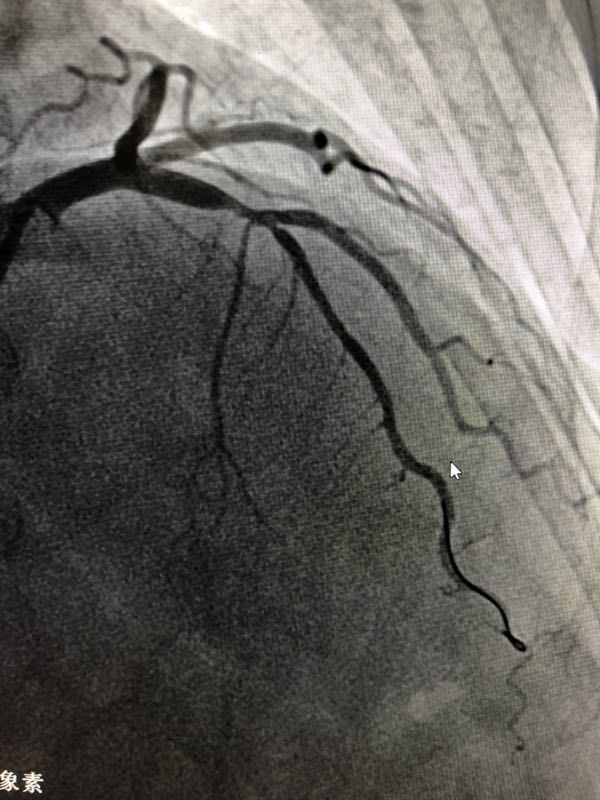

重庆医科大学附属第二医院心内科殷跃辉教授团队陈国柱副主任医师今日成功实施重庆首例 “生物可吸收心脏支架”植入术。在殷跃辉主任指导、刘增长、凌智瑜教授的协助下,留德归来的陈国柱博士应用先进的血管内超声影像技术及Visual Histology分析技术,指导可吸收支架的选择,同时严格执行生物可吸收支架植入规范化PSP操作,3.0x18mm支架完美释放,后扩张后贴壁良好,手术非常成功!帮助患者实现冠脉血管重建。

NeoVas生物可吸收支架是继金属支架“血管再通”后心血管治疗领域的又一次革命。它有效避免了金属支架植入后血管僵硬度增加的风险。术后1-3年体内支架可完全降解,基本恢复病变血管的弹性舒缩功能,实现血管再造的效果,且体内不遗留其他成分,避免众多患者的异物担忧。预计未来可吸收支架会被广泛使用,冠心病介入疗将进入新的时代。